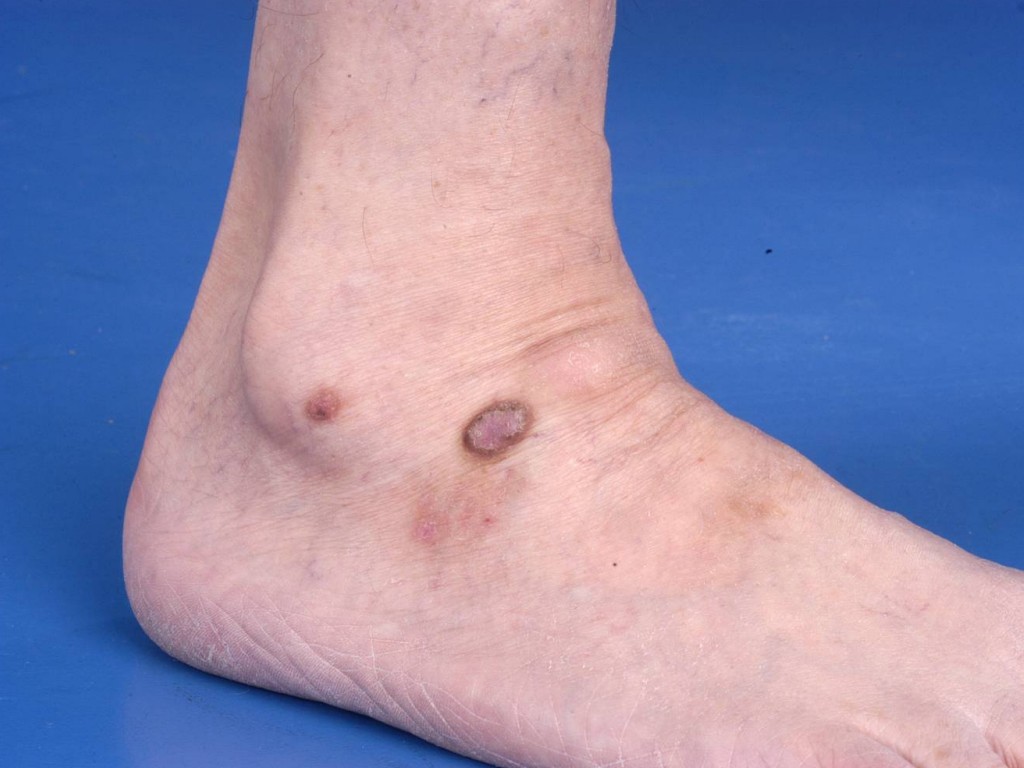

WHAT IS A DERMATOFIBROME?A dermatofibroma, also called a histiocytoma, is a slow-growing, firm or hard bump in the skin, usually on the lower legs. It is a benign skin condition.WHAT DOES A DERMATOFIBROMA LOOK LIKE?It's usually a hard bump on a leg. It can be skin-colored, red, or brown. A dermatofibroma is usually slightly sunken, with the majority of the area located in and under the skin. A dermatofibroma contains a lot of connective tissue (scar tissue), which can cause the area to become attached to the underlying surface. If you try to lift a skin fold at the spot, the dermatofibroma won't lift, creating a small indentation. This is called the dimple sign. Dermatofibromas can also appear on the arms and other parts of the body. There can be one or several at once. They cause few symptoms, sometimes pain or itching.

![Dermatofibroma (click on photo to enlarge) [source: www.skin-diseases.eu] Dermatofibroma](../../images/dermatofibroom-3z.jpg) |

| dermatofibroma |

dermatofibroma |